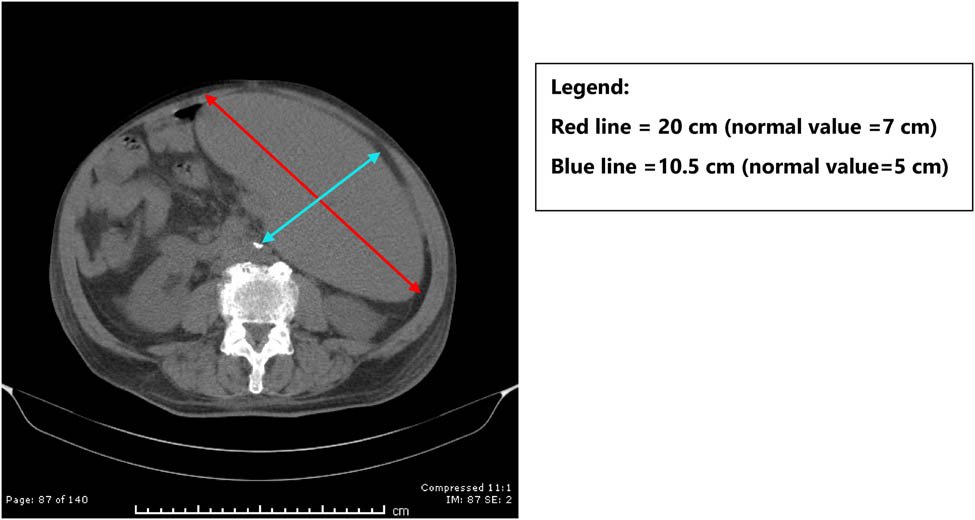

In early November 2019, the patient sought oncology consult where a computerized axial tomography (CT) scan revealed massive splenomegaly with dimensions of 22 cm × 10.5 cm × 20 cm, (normal spleen size: 12 cm × 5 cm × 7 cm; Figure 2), mediastinal lymphadenopathy, but no significant atherosclerotic changes or cardiomegaly were observed. However, serum immunoglobulins, albumin, and total protein were all low. Hypogammaglobulinemia is one of the criteria for malignant transformation of CLL [25]. His oncologist’s diagnosis was a malignant transformation to lymphoma, and he recommended immunotherapy with rituximab and ibrutinib. This is particularly important because advanced CLL is usually treated with corticosteroids, rituximab, or ibrutinib. With occult babesiosis in the background, these treatments could have been deadly as has been reported previously [24].

CT scan showing massive splenomegaly.